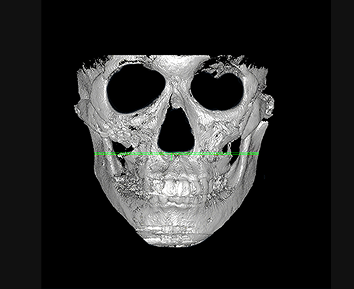

Targeting the areas with the greatest protrusion

ID Hospital’s contouring revision surgery reduces the most protruding areas

of the cheekbone using the High-L osteotomy/reduction method,

minimizing excessive bone removal while effectively reducing volume.

Jaw angle revision surgery addresses the maximal volume point (MVP) that defines the jawline, reducing it to create a slimmer and more refined

facial contour visible from every angle.